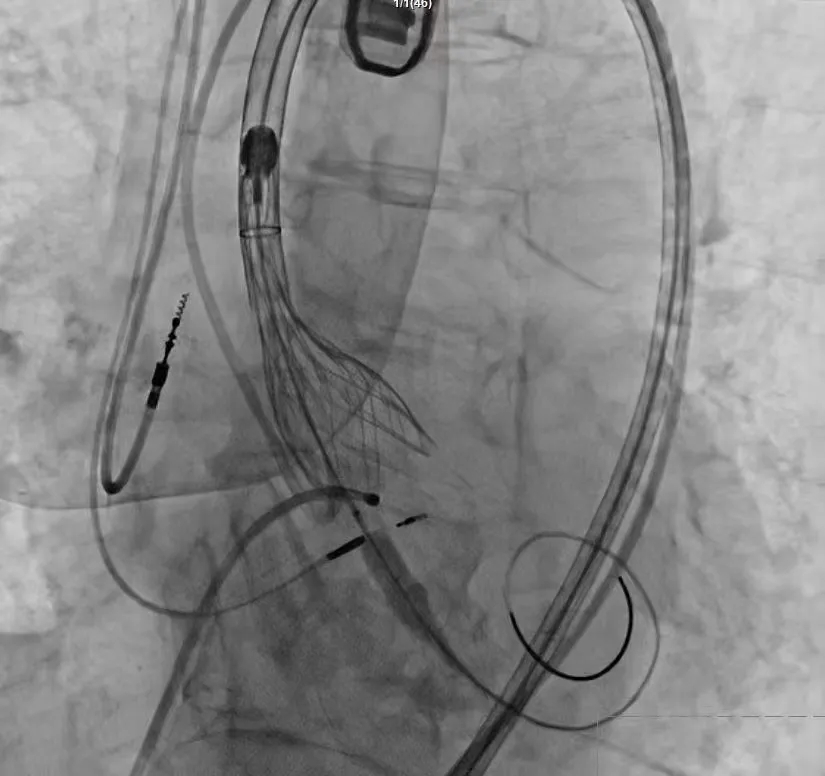

手术过程严谨有序:经术前精准评估与周密准备,团队成功送入预先装载的自膨式支架瓣膜输送系统,顺利完成过弓、跨瓣操作;经造影定位后,在180bpm快速起搏下精准释放瓣膜。瓣膜释放后,术中实时超声显示根部瓣架形态良好、启闭正常,瓣叶中心及瓣周未见反流;造影显示瓣膜位置满意、形态良好,冠脉显影清晰,入路血管无损伤,历经90分钟后,手术圆满成功。

术中影像

术后患者跨瓣压差从58mmHg降至8mmHg,主动脉瓣反流完全消失,5天后患者顺利出院。